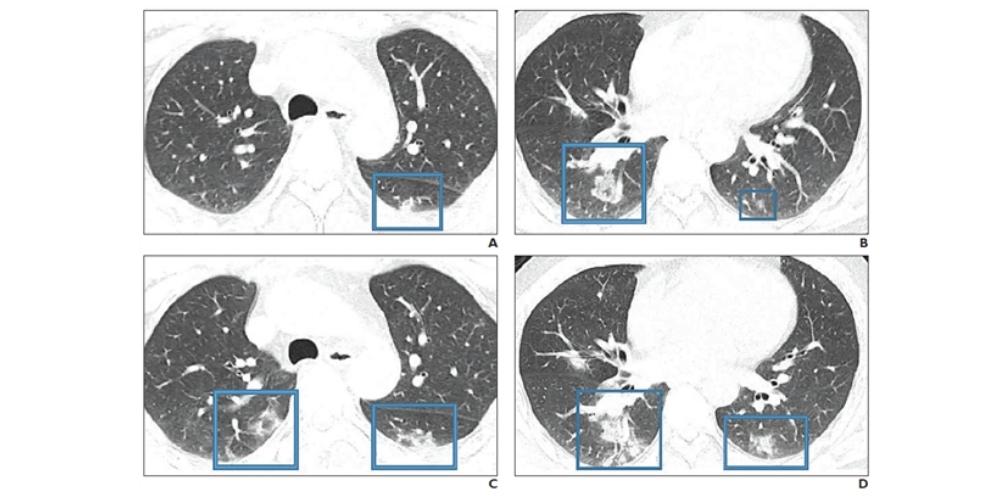

“An investigation of initial chest CT findings in 21 individuals with confirmed COVID-19 reported abnormal findings in 86% of patients, with a majority having bilateral lung involvement,” the authors wrote.

Moreover, in addition to the bilateral lung involvement factor, the three viruses also differ in the features that indicate a poor prognosis, according to Dr. Hosseiny’s research group:

- SARS: Bilateral (like acute respiratory distress syndrome), four or more lung zones, progressive involvement after 12 days

- MERS: Greater involvement of the lungs, pleural effusion, pneumothorax

- COVID-19: Consolidation (versus ground-glass opacity)